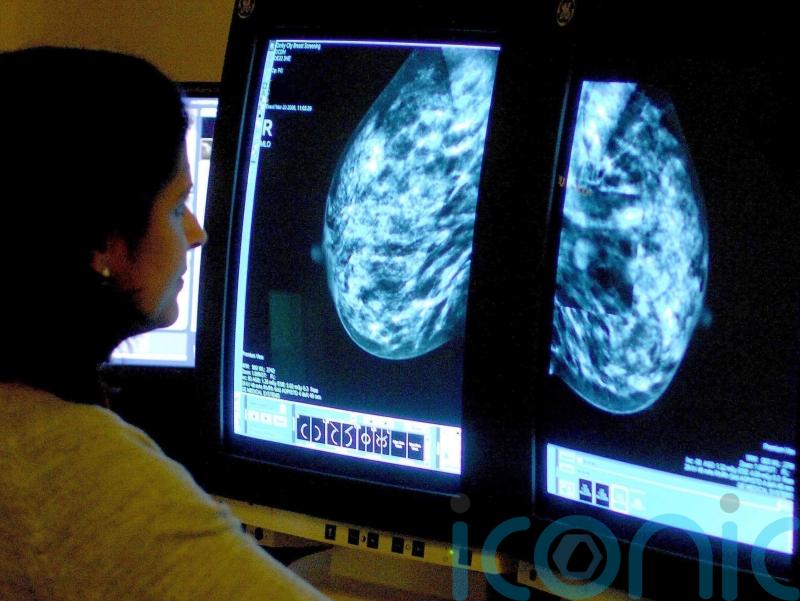

One in 20 women referred urgently for breast cancer were seen within two weeks last winter, figures released by the Department of Health show.

From October to December 2025, 3,902 patients were seen by a breast cancer specialist after an urgent referral across all five HSC Trusts, 44.6% more than in the previous quarter.

Some 5.5% of those patients were seen within 14 days of an urgent referral for breast cancer, compared with 6.8% in the previous period.